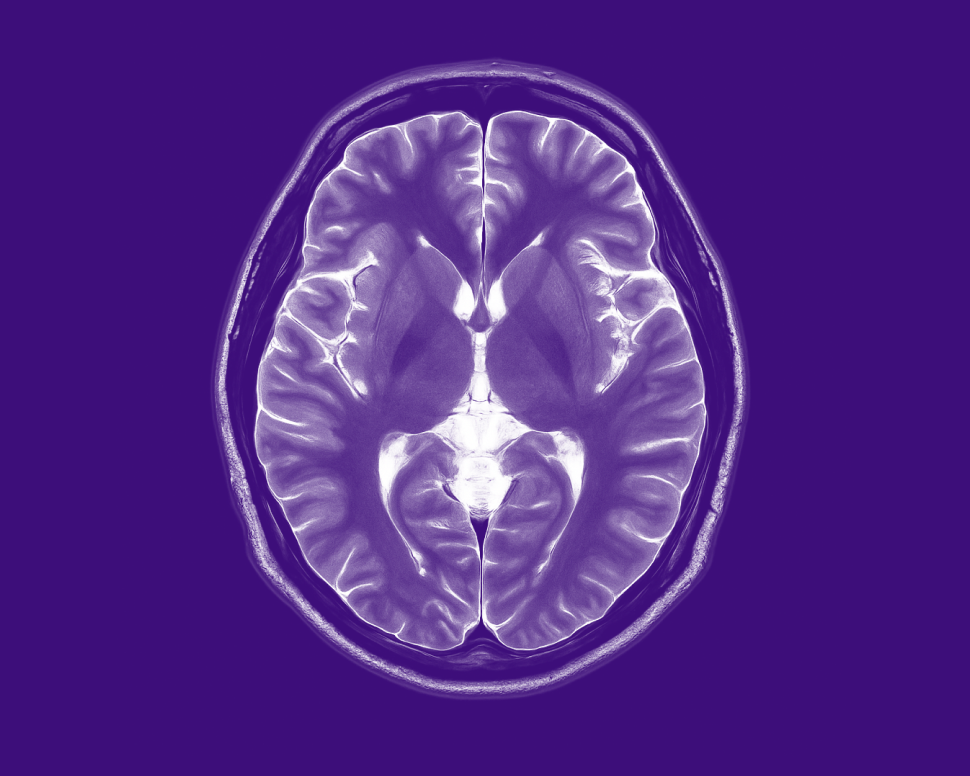

For years, women were given this birth control shot without being warned about the risk of brain tumors. Now, those women are stepping forward.